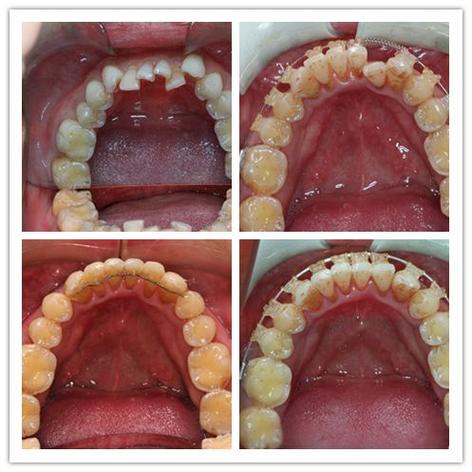

1、刘先荣医师是院内口腔美容中心骨干专家,专注牙齿矫正与种植领域12年,熟练掌握隐适美隐形矫正、全口种植等先进技术。刘医生注重咬合功能与面部美学的协调统一,其独创的"三维美学正畸方案"获得省级医疗技术创新奖。

2、陈科屹主治医师作为口腔整形专家,在美学修复领域具有突出成就。陈医生先后赴德国、瑞士进修显微美学修复技术,擅长前牙美学贴面、全瓷冠修复等精细项目,其操作的病例多次入选行业学术案例库。